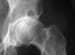

In the osteoarthritic hip (see the image below), the superior aspect of the joint is typically the most narrowed; axial and medial migration of the femoral head is less commonly seen.

Anteroposterior (AP) radiograph of the hip reveals severe superior migration of the femoral head (which reflects loss of articular cartilage), subchondral sclerosis, prominent osteophytes, and a large Egger cyst in the superior acetabulum. Mild flattening of the superior aspect of the femoral head is present.